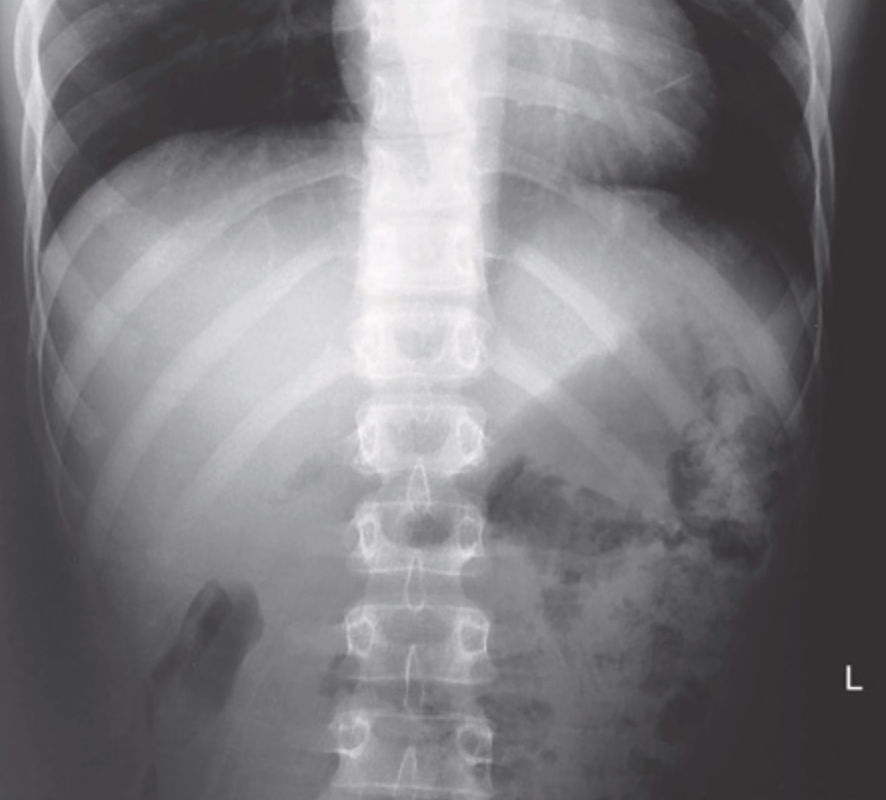

what is this radiograph

posteroanterior of sternoclavicular joints

what is this projection called

bilateral PA SC joint

what is this viewing?

right SC joint

what is the radiograph name

Pa oblique SC joint